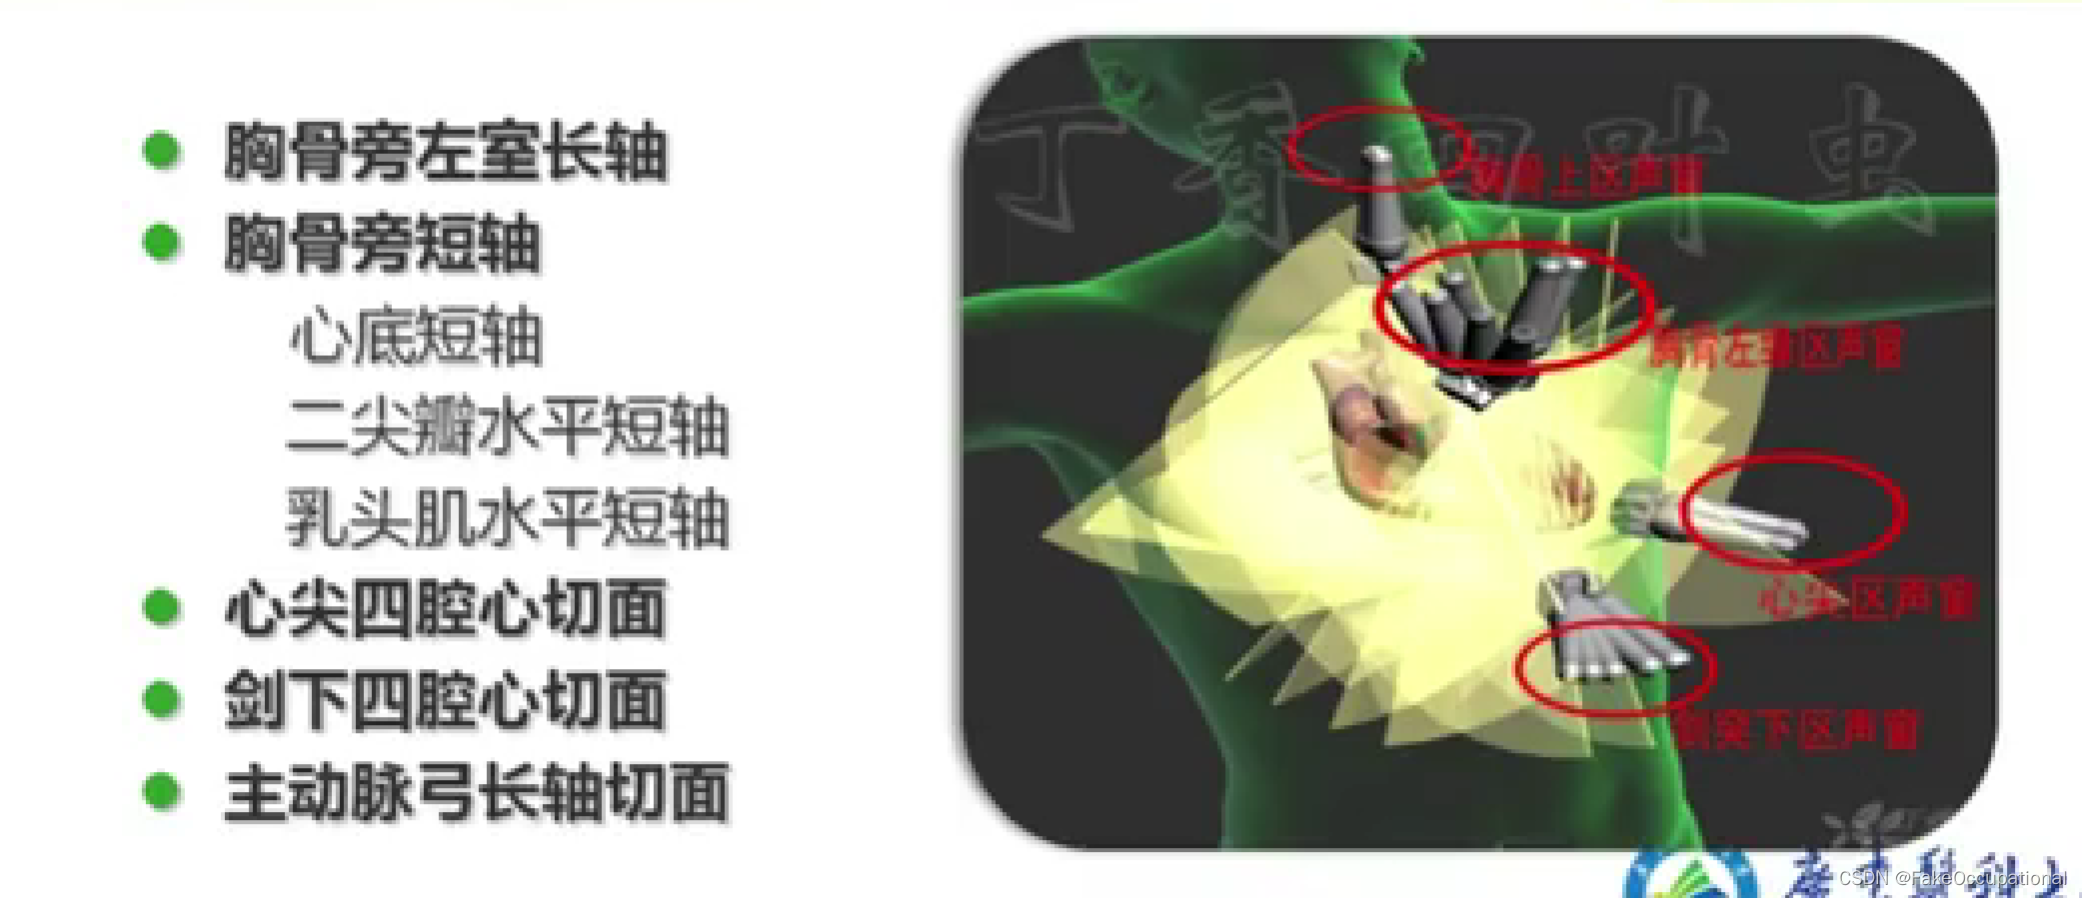

超声心动图检查方法

- 仪器选择常用电子相控阵探头

- 经胸扫查

- 成人2.5-4.0MHz新生儿和儿童5.0-7.0MHZ